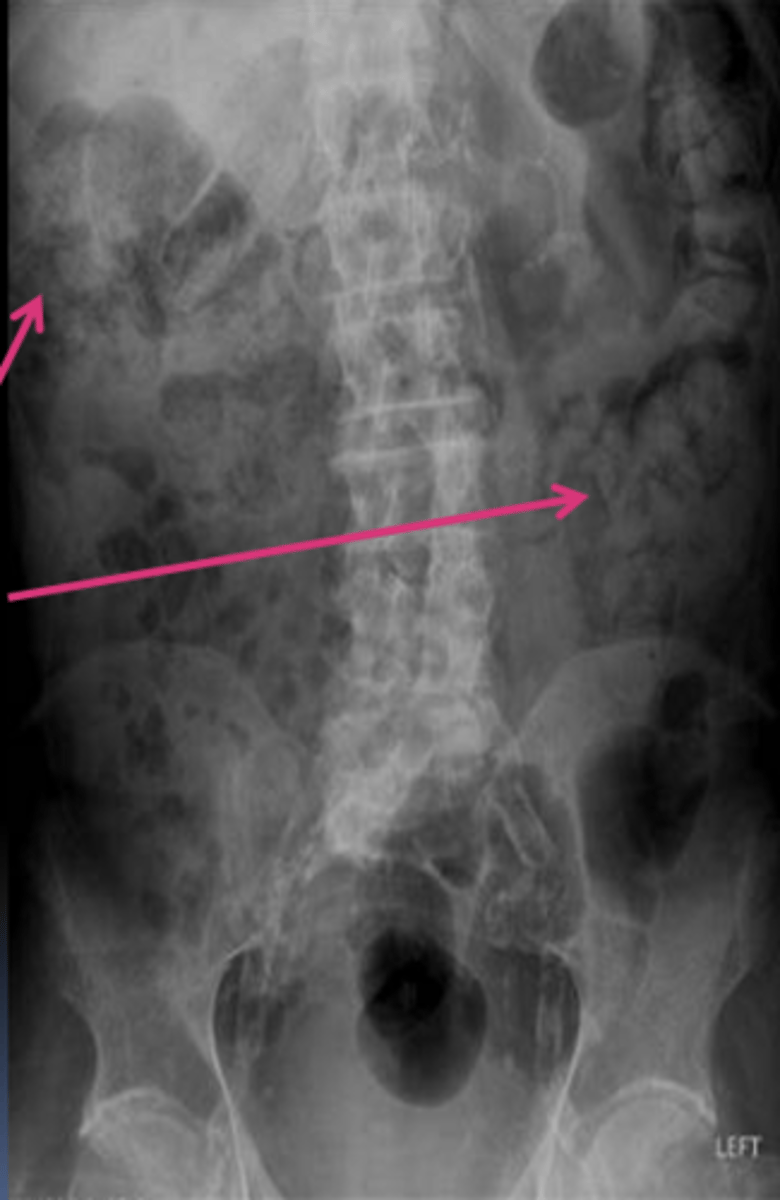

large bowel

Stool on x-ray marks the presence of what?

stool

What are the arrows pointing to?

Where should we NOT see (or see very few) air-fluid levels on X-ray?